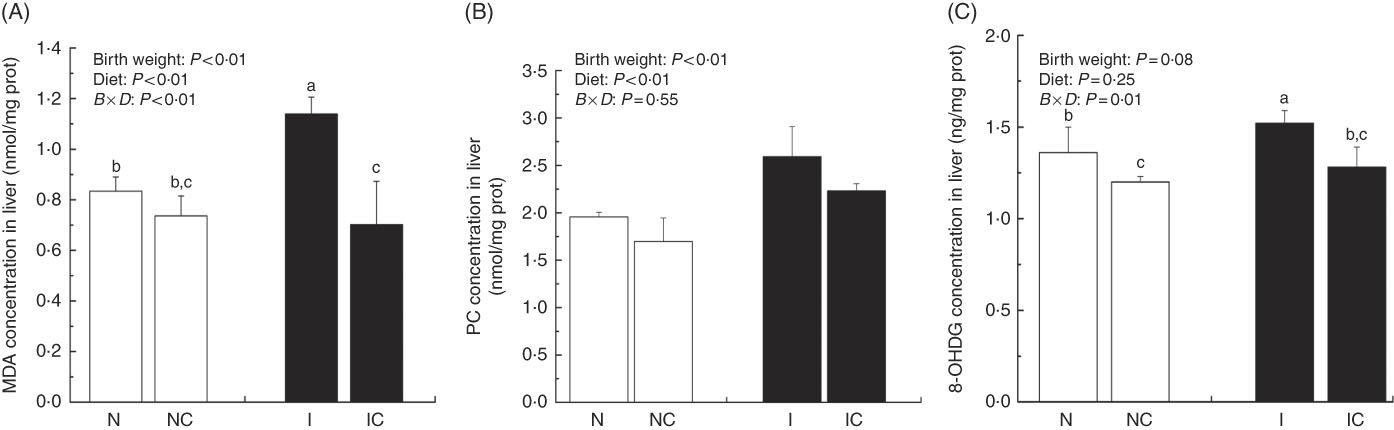

Hepatic lipid peroxidation, protein and DNA oxidation levels

The concentrations of MDA, PC and 8-OHDG in the liver of IUGR rats were significantly higher (P<0·05) than those of NBW rats (Fig. 5(A)–(C)). In addition, a birth weight×dietary interaction effect was noted for liver concentrations of MDA and 8-OHDG in rats. Dietary curcumin supplementation significantly decreased the concentrations of MDA, PC and 8-OHDG in the liver of IUGR rats (P<0·05).

Fig. 5 Concentrations of malondialdehyde (MDA) (A), protein carbonyl (PC) (B) and 8-hydroxy-2'-deoxyguanosine (8-OHDG) (C) in the liver of normal birth weight rats (N), normal birth weight rats supplemented with curcumin (NC), intra-uterine growth retardation (IUGR) rats (I) and IUGR rats supplemented with curcumin (IC) (12 weeks of age). Values are means (n 6) and standard deviations. ![]() , Normal birth weight;

, Normal birth weight; ![]() , IUGR; B, birth weight; D, diet; B×D, interaction between the corresponding parameters. Data were analysed by using two-way ANOVA. a,b,c Mean values with unlike letters were significantly different when a significant interaction was observed (P<0·05).

, IUGR; B, birth weight; D, diet; B×D, interaction between the corresponding parameters. Data were analysed by using two-way ANOVA. a,b,c Mean values with unlike letters were significantly different when a significant interaction was observed (P<0·05).